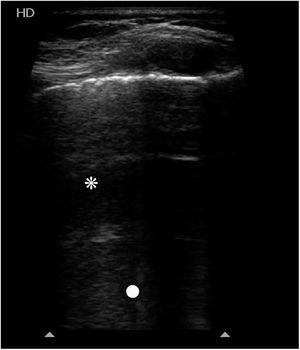

Niño de 6 años intervenido de Fontan. Tras su extubación fracasa por bronquitis plástica (BP). A los 4 días presenta hipofonesis del lóbulo superior derecho (LSD). Por ecografía pulmonar se observan líneas A (asterisco), algunas líneas B (punto blanco), con pulso de pulmón, pero sin deslizamiento pleural, sin áreas de condensación. El resto del pulmón está bien aireado, con deslizamiento pleural y sin imágenes patológicas. Se descarta neumotórax (fig. 1), pero llama la atención la ausencia de deslizamiento pleural. A los 3 días se observa un aumento de densidad en el LSD (fig. 2), sin correlación clínica. A los 15 días presenta insuficiencia respiratoria aguda progresiva con mejor aireación del hemitórax derecho por radiografía (fig. 3A), pero se colapsa a las 7h (fig. 3B). Por broncoscopia rígida se extrae un nuevo molde de BP (fig. 3C). La ecografía pulmonar permite la identificación precoz de áreas mal aireadas, sin deslizamiento pleural, previo a la consolidación. Esta imagen podría ser un indicador temprano de BP en pacientes en riesgo de presentarla, y el uso seriado de la ecografía pulmonar podría facilitar su control evolutivo.